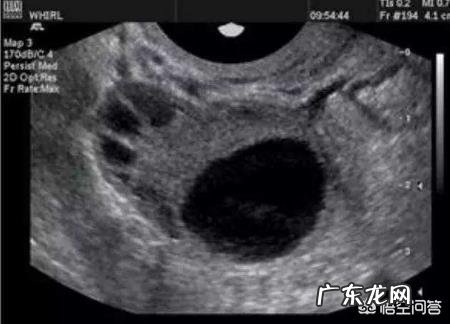

文章插图